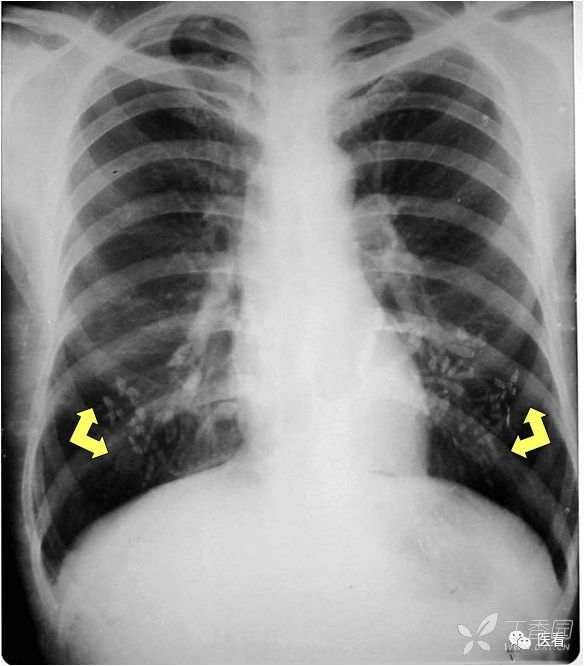

肺坠积效应

由于血液因引力作用向近地侧沉积,因此两肺下叶背侧胸膜下带血液相对较多,双肺后部肺野密度增高(箭示),称之为坠积效应。在老年人及长期卧床者尤其明显。如果不认识可能误认 为肺内炎症或肺间质纤维化。

胸膜外脂肪

如果不认识,有可能误认为是胸 腔积液。

识别的方法:1.其密度与皮下 脂肪相同;2.该影不随体位变化。